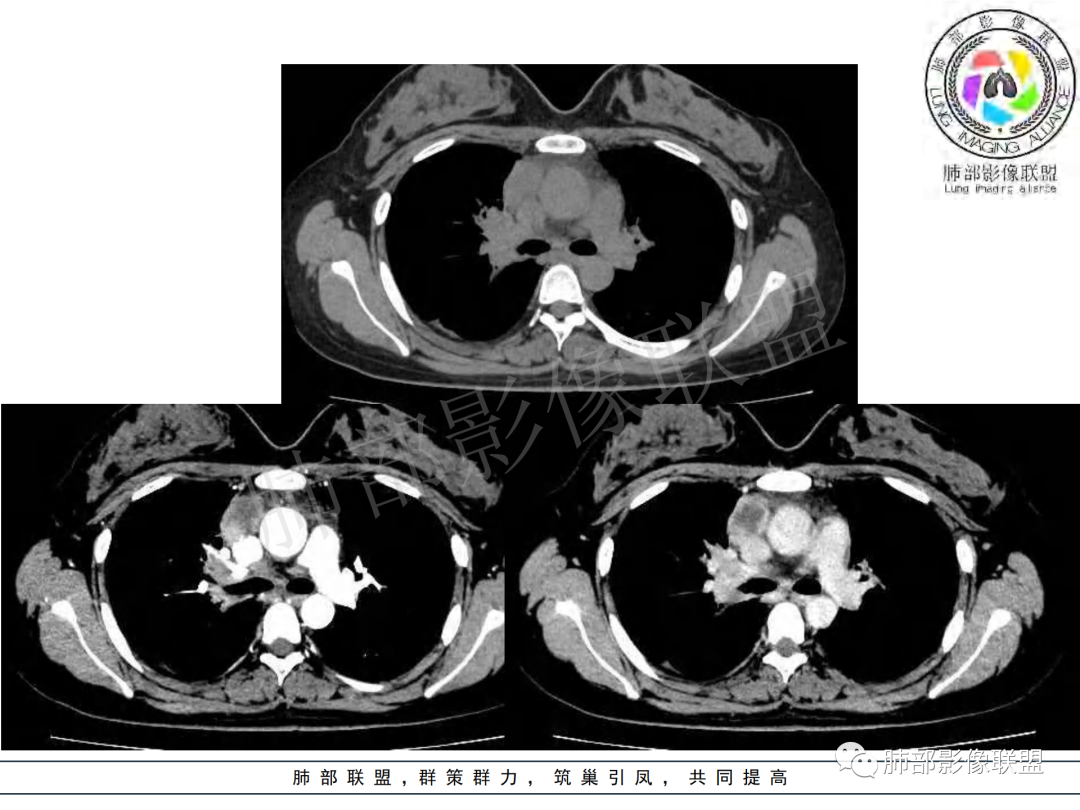

右肺肺门旁肿块,右肺中间段支气管腔内结节,增强强化不均;纵隔多发淋巴结环形强化,右侧少量胸腔积液,临床发热入院,考虑结核,鉴别肿瘤。

右肺门增大,远端花花草草不明显,支气管管壁增厚,纵隔淋巴结环形强化,年龄,病程,考虑炎性病变,结核可能,有个层面支气管截断,有强化,鉴别粘表。

纵隔多组及右侧肺门多发肿大淋巴结,部分融合,不均匀强化,内见斑片状坏死区及环状强化,后者坏死边界尚清晰,肺门区肿大淋巴结与肺组织边界不清,年轻女性,8个月病史,发热首发症状,考虑淋巴结核并向肺内侵及(破溃?),鉴别淋巴瘤

女,20,病程长达8月,发热、胸痛、右侧胸腔积液病史。胸部CT:右肺门旁不规则肿块影,右中间支气管腔内结节,纵隔多发淋巴结肿大;强化不均匀,灶性坏死灶,环形强化;右侧少量胸腔积液并局部肉芽肿样突起。年轻女性,长病程,多部位,考虑慢性炎症,结核?鉴别肿瘤。

青年,右肺门增大,见软组织肿块影,部分支气管腔结节,并管腔狭窄,增强后明显不均匀强化,伴纵隔多发肿大淋巴结,环形强化,考虑恶性,类癌,鉴别支气管内膜结核

右肺门不规则肿块,向气管腔内生长,不均匀强化,其内粘液栓,纵隔淋巴结增大,部分有坏死,胸膜结节强化,考虑恶性,粘表?类癌?鉴别结核

右肺肺门旁肿块,右肺中间段支气管腔内结节,增强强化不均;纵隔多发淋巴结环形强化,右侧少量胸腔积液,考虑结核可能,鉴别肿瘤。

年轻女性,慢性病程,发热、胸痛。右肺门旁不规则肿块影,纵隔多发淋巴结肿大;强化不均匀,环形强化;右侧少量胸腔积液;首先考虑结核,鉴别肿瘤,结节病。

右肺门及纵膈多发淋巴结肿大,部分融合,密度不均,部分呈环形强化,年轻女性,病史长,发热,考虑淋巴结结核

女性,20岁。高热、畏寒。右肺上叶近肺门区不规则肿块,周围斑点、片小结节影伴肿大淋巴结,肿块包绕并突入右主支气管腔内,增强后肿块不均匀强化,淋巴结环形强化中心低密度,考虑结核。

本例患者,年轻女性,慢性病程,多次抗感染治疗效果不佳,实验室检查示白细胞及中性粒细胞不高,不支持普通细菌感染,虽然肺泡灌洗液X-Pert检测阴性,结合患者胸部CT结核感染亦不能排除,胸部CT主要表现为右侧肺门及纵隔淋巴结肿大,仔细观察不难发现右中间支气管内新生物凸向管腔内,增强扫描,右肺门(10R)及纵隔淋巴结(2R,4R)明显不均匀强化,内部呈不规则低密度无强化区,被周边高强化区包绕(环形强化)的特点,首先应当想到纵隔淋巴结结核诊断。淋巴结分布亦不符合肺部恶性肿瘤迁徙途径。